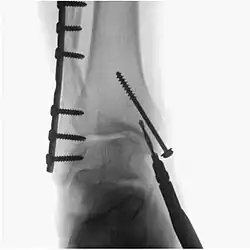

A fluoroscopy X-ray machine is a great asset during surgery for implants

Surgical fluoroscopy

Fluoroscopy is used in various types of surgical procedure, such as orthopaedic surgery and podiatric surgery. In both of those, it is used to guide fracture reduction and in use in certain procedures that have extensive hardware. Specifically, once the fracture is realigned, a surgeon will (with the assistance of their surgical technologist) drill a guide pin into the bone tissue and use fluoroscopy to insure proper angle of the pin - then a cannulated drill bit is inserted over the pin to prepare a ‘hole’ for a bone screw. If the surgeon prefers a different angle, they simply reverse the pin and redrill. Fluoroscopy will be use for each screw placed -which has greatly improved proper fracture heal due to more accurate reduction.[5]